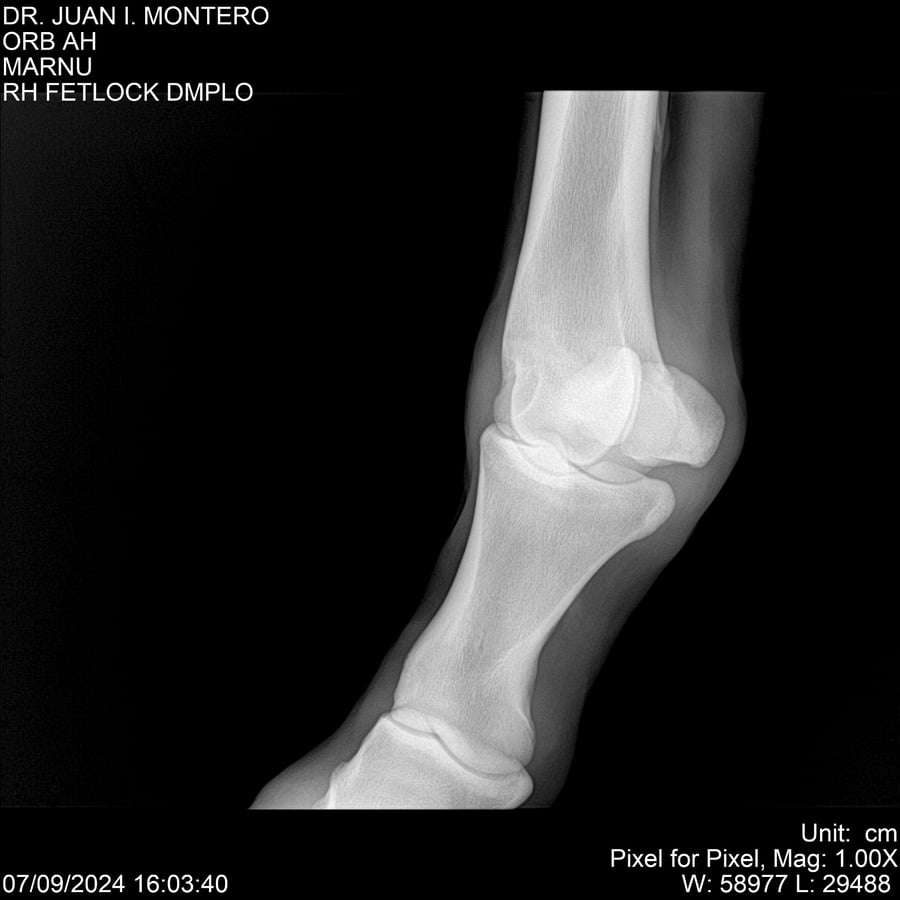

LOTE 21, ORB AH Lote Anterior Volver al remate Lote Siguiente Ficha Contacto Montevideo - Ficha del Lote Identificador: #282519 Categoría: Yeguarizos Montevideo - 57 Visualizaciones ClicData Contacto Empresa: Abelenda N. R., Walter Hugo Nombre*: Teléfono* : E-mail* : Mensaje Enviar Registrese gratis Este contenido Exclusivo está disponible sólo para usuarios registrados Ingresar